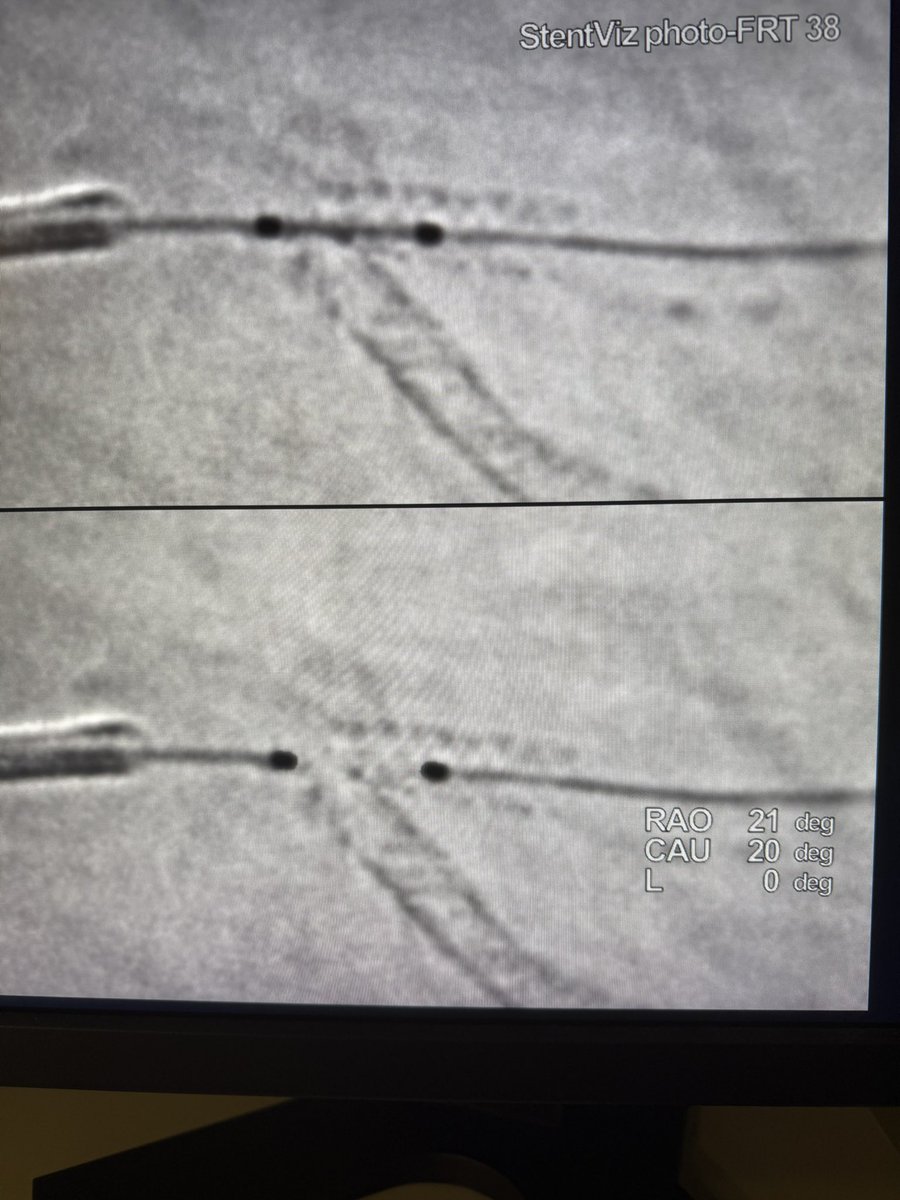

F/u to previous post. Stent boost is terrific! Clearly defined the problem. Prep a cutter and high psi NCs. 3.0 agent and a KBI to finish.

2

0

9